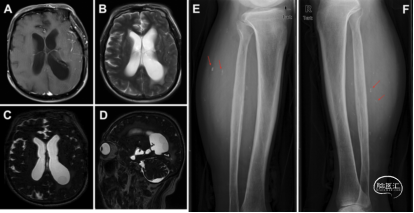

● 一是高分辨率3D SPACE MRI的应用:常规T1或T2加权MR图像上,囊肿内容物信号强度与CSF相似,囊壁通常不清晰,导致IVSN难以诊断。研究人员纳入了高分辨率、重T2加权的3D SPACE(sampling perfection with application-optimized contrast using different flip angle evolutions)序列。结果显示:3D SPACE MRI在所有病例中(100%)都能清晰地显示虫囊包膜,其内容物在3D SPACE图像上呈现出比CSF显著较低的信号强度。

● 二是下肢侧位X线片检查作为诊断辅助:研究将下肢侧位X线片纳入术前影像协议,用于筛查下肢肌肉中的微小肌内钙化。结果显示:在51例患者中,有48例(94.1%)通过下肢X线片发现了肌内钙化。该方法的检出率高于传统的血清ELISA囊虫抗体检测(阳性率为88.2%)。这是首次报道将下肢侧位X线片作为诊断辅助手段,它是一种经济有效且易于获取的筛查方法。